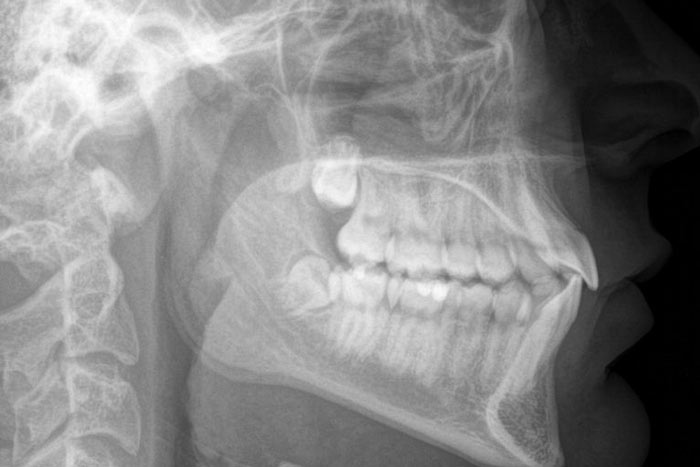

Hierfür greift der Kieferorthopäde auf das Fernröntgenseitenbild zurück. Diese zweidimensionale Aufnahme zeigt, wie die Kiefer zueinander positioniert sind und wie die Frontzähne im Knochen stehen. Dies ist entscheidend, um sicherzustellen, dass die Zähne innerhalb des sicheren Kieferknochens bewegt werden und keine Schäden entstehen.

Bei Kindern und Jugendlichen gibt das Fernröntgenseitenbild Aufschluss über die Wachstumsrichtung der Kiefer, was für die Planung des Therapiezeitpunkts und die Auswahl der Zahnspange entscheidend ist.